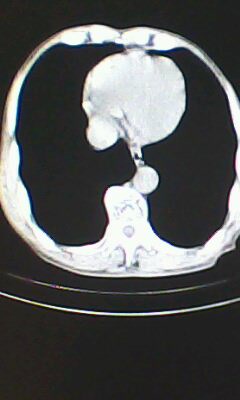

胸廓呈桶状,双膈低平,肺实质及纵隔未见明显异常密度灶考虑肺气肿.

肺气肿

做个肺功能检查。肺ct无明显异常。

临床诊断:copd

慢阻肺是临床诊断,未见明显异常。